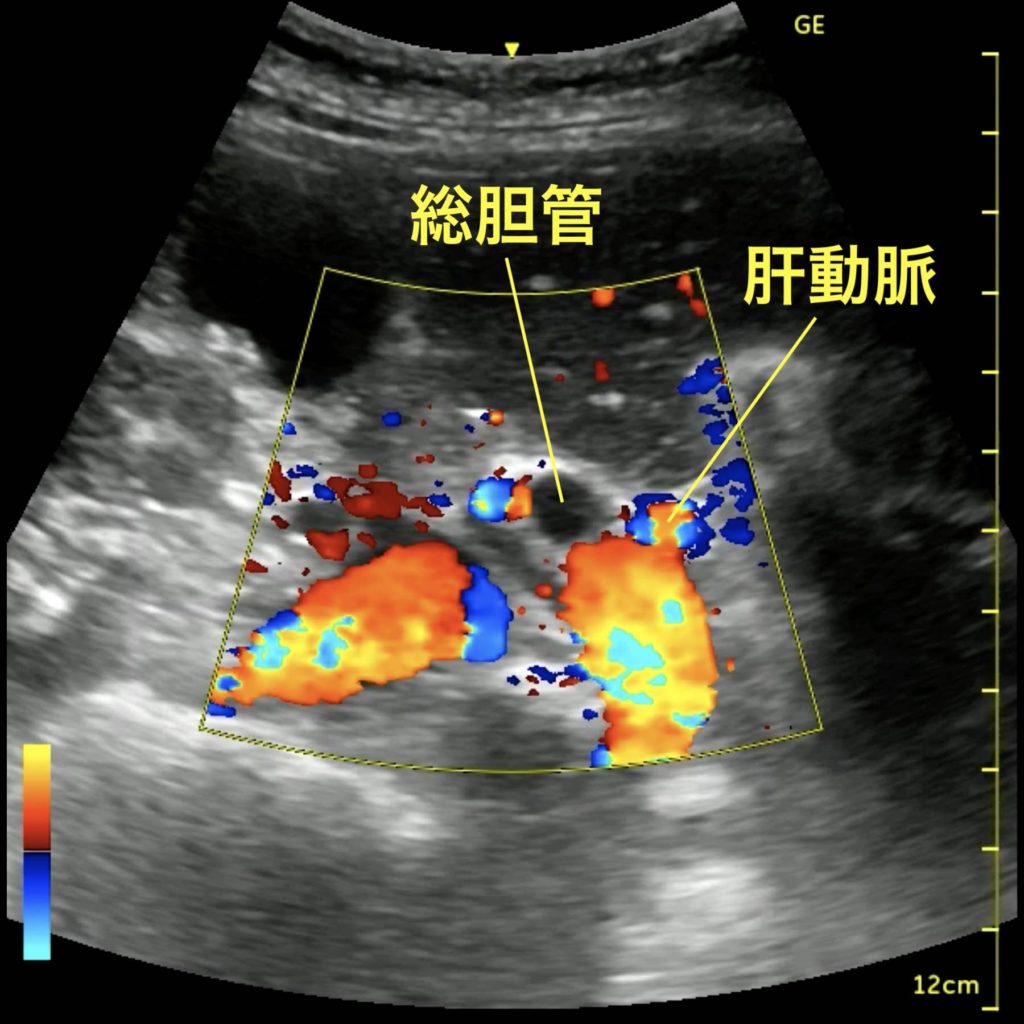

救急外来。発熱、腹痛。みられる異常はなにか?

総胆管の拡張

総胆管の同定は、胆嚢と右門脈との位置関係によって行うのが比較的容易である。門脈の浅側には肝動脈と総胆管が3つ組になって存在しており、血流のない方が総胆管である。通常は冠動脈も総胆管も同程度の径であるが、この画像のように一方が拡張している場合は総胆管の閉塞が示唆される。症候群からは閉塞性化膿性胆管炎が疑われる。